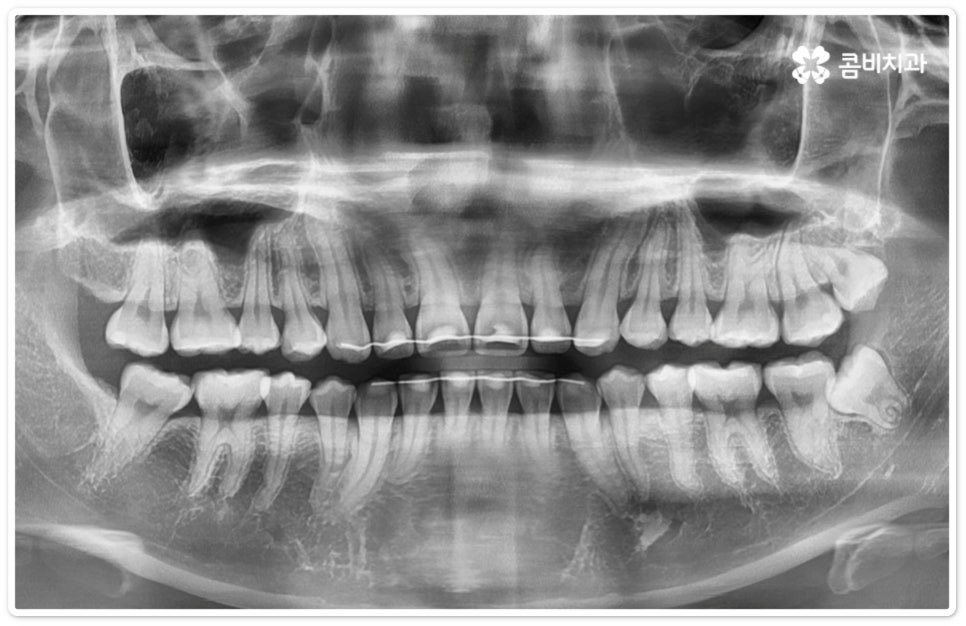

사랑니의 개수, 위치, 각도나 뿌리의 형태, 매복 깊이 등은 사람마다 다른데 그 중에서 특히 완전히 매복된 상태로 비스듬히 누운 채 자리잡은 아래 사랑니의 경우 턱을 가로지르는 하치조 신경과 가깝기 때문에 누운사랑니발치 시 신중을 기하지 않으면 혹시 모를 부작용인 감각 이상을 초래할 수 있으므로 뛰어난 해부학적 지식과 풍부한 임상 경험, 세심한 기술력을 가지고 있는 숙련된 의료진에게 치료를 받으시길 권유드리고 있어요. 혹시라도 신경 손상이 발생하게 되면 입술이나 턱이 마취된 듯 침이 흘러도 감각이 없거나 양치질을 할 때 물이 입술밖으로 세어나가는 상태가 유발될 수 있으니 조심해야 할 거예요.

매복 형태의 사랑니는 잇몸을 절개하고 발치해야 하며, 특히 깊숙하게 누운사랑니발치 시에는 신경을 건드리지 않도록 사랑니를 조각내어 조심해서 빼내야 할 뿐 아니라 환자분들의 상태에 따라 잇몸뼈를 조금씩 삭제해야 할 수도 있기 때문에 이러한 고난도 시술에는 주변 조직의 손상을 최소화하고 혹시 모를 부작용의 위험을 줄이며 출혈 및 통증이 커지지 않도록 하기 위해서 시술자의 높은 숙련도가 더욱 요구된다고 할 수 있어요. 또한 매복된 사랑니의 각도, 뿌리 형태, 인접 치아와의 관계, 신경 위치 등을 정확하게 파악하고 체계적인 맞춤 계획을 세워 무리하지 않게 사랑니 발치 수술을 진행하기 위해서 정밀 진단이 가능한 3D CT 장비가 있는 치과에서 꼼꼼한 검사부터 받아보는 것이 중요할 거예요.